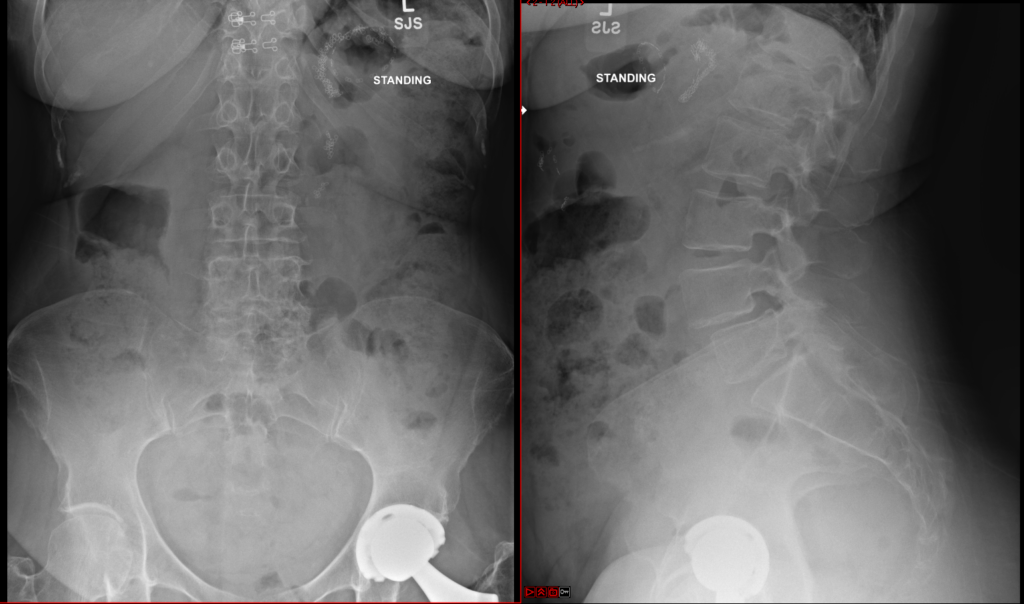

Anterior Lumbar Interbody Fusion